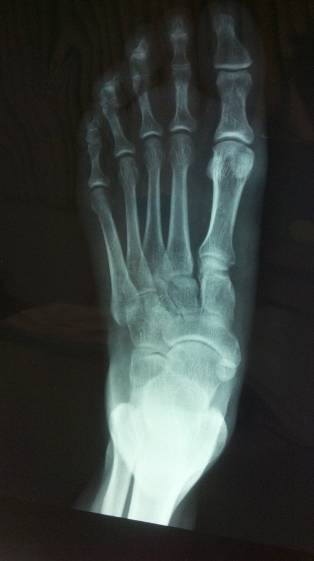

L’Osteonecrosi és una malaltia que es produeix per la pèrdua de flux de sang a l'interior dels ossos (isquèmia). Sense reg de sang el teixit mor (necrosi) i es debilita l'os.

Si es produeix prop d'una articulació pot arribar a alterar-la i propiciar l'aparició d'artrosi de forma més precoç. Generalment els ossos afectats inclouen el maluc, l'espatlla, el genoll, el colze, el canell i el turmell.